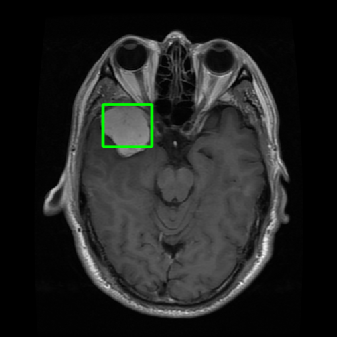

From the above discussions, we have discovered the significant potential of applying Retinex theory to image segmentation and explored its fundamental differences from traditional models. Traditional image segmentation models typically focus on the impact of intensity information on the segmentation results. Therefore, when faced with complex segmentation scenarios, the segmentation results are often affected by lighting, artifacts, and unclear boundaries in the image. As shown in Fig. 1, we present the results of the classical local model LIF [ZHANG20101199] for segmenting brain tumor images along with surrounding tissue edema. The irregular ring-like enhancement caused by the edematous tissue leads to irregular boundaries and low contrast in the images. Consequently, the LIF model can only identify the central necrotic and liquefied regions of the tumor, failing to detect the boundaries and becoming trapped in local minima. In this paper, we draw inspiration from the Retinex theory, which is widely applied in the field of image enhancement. According to Retinex theory, the reflectance component characterizes the intrinsic structural properties of the observed image and preserves texture information independent of illumination variations. By integrating this reflectance component into the level set framework, our model achieves robust segmentation of medical images even under severe intensity inhomogeneity. In addition, a linearized Structural-Prior is proposed to restore intensity consistency and capture local geometric features, thereby improving boundary localization in complex or blurred regions. Furthermore, a relaxed binary level set representation is employed to enhance robustness against noise and to enable accurate tracking of complex contours. Based on these innovations, we propose a novel variational reflectance-based level set model (RefLSM) that simultaneously corrects bias fields and performs segmentation. Experimental results demonstrate that RefLSM significantly outperforms conventional level set methods in both segmentation accuracy and robustness. We present the results of our model segmenting the two brain tumor images mentioned above in Fig. 2.

To address the challenge of segmenting images with severe intensity inhomogeneity, we propose a linearized structural prior that directly operates on the reflectance component . Reflectance-based structural information is more robust to illumination variations and bias field distortions, helping preserve weak edges and subtle anatomical boundaries. As shown in Fig. 2, our method can accurately delineate tumor boundaries and surrounding edema even under severe inhomogeneity, where traditional intensity-based models often fail. The proposed prior aligns smoothed reflectance gradients with data-driven directions, enhancing inter-region contrast, preserving weak edges, and stabilizing the evolution of . Formally, we define the linear structure operator as the gradient field of the smoothed reflectance: